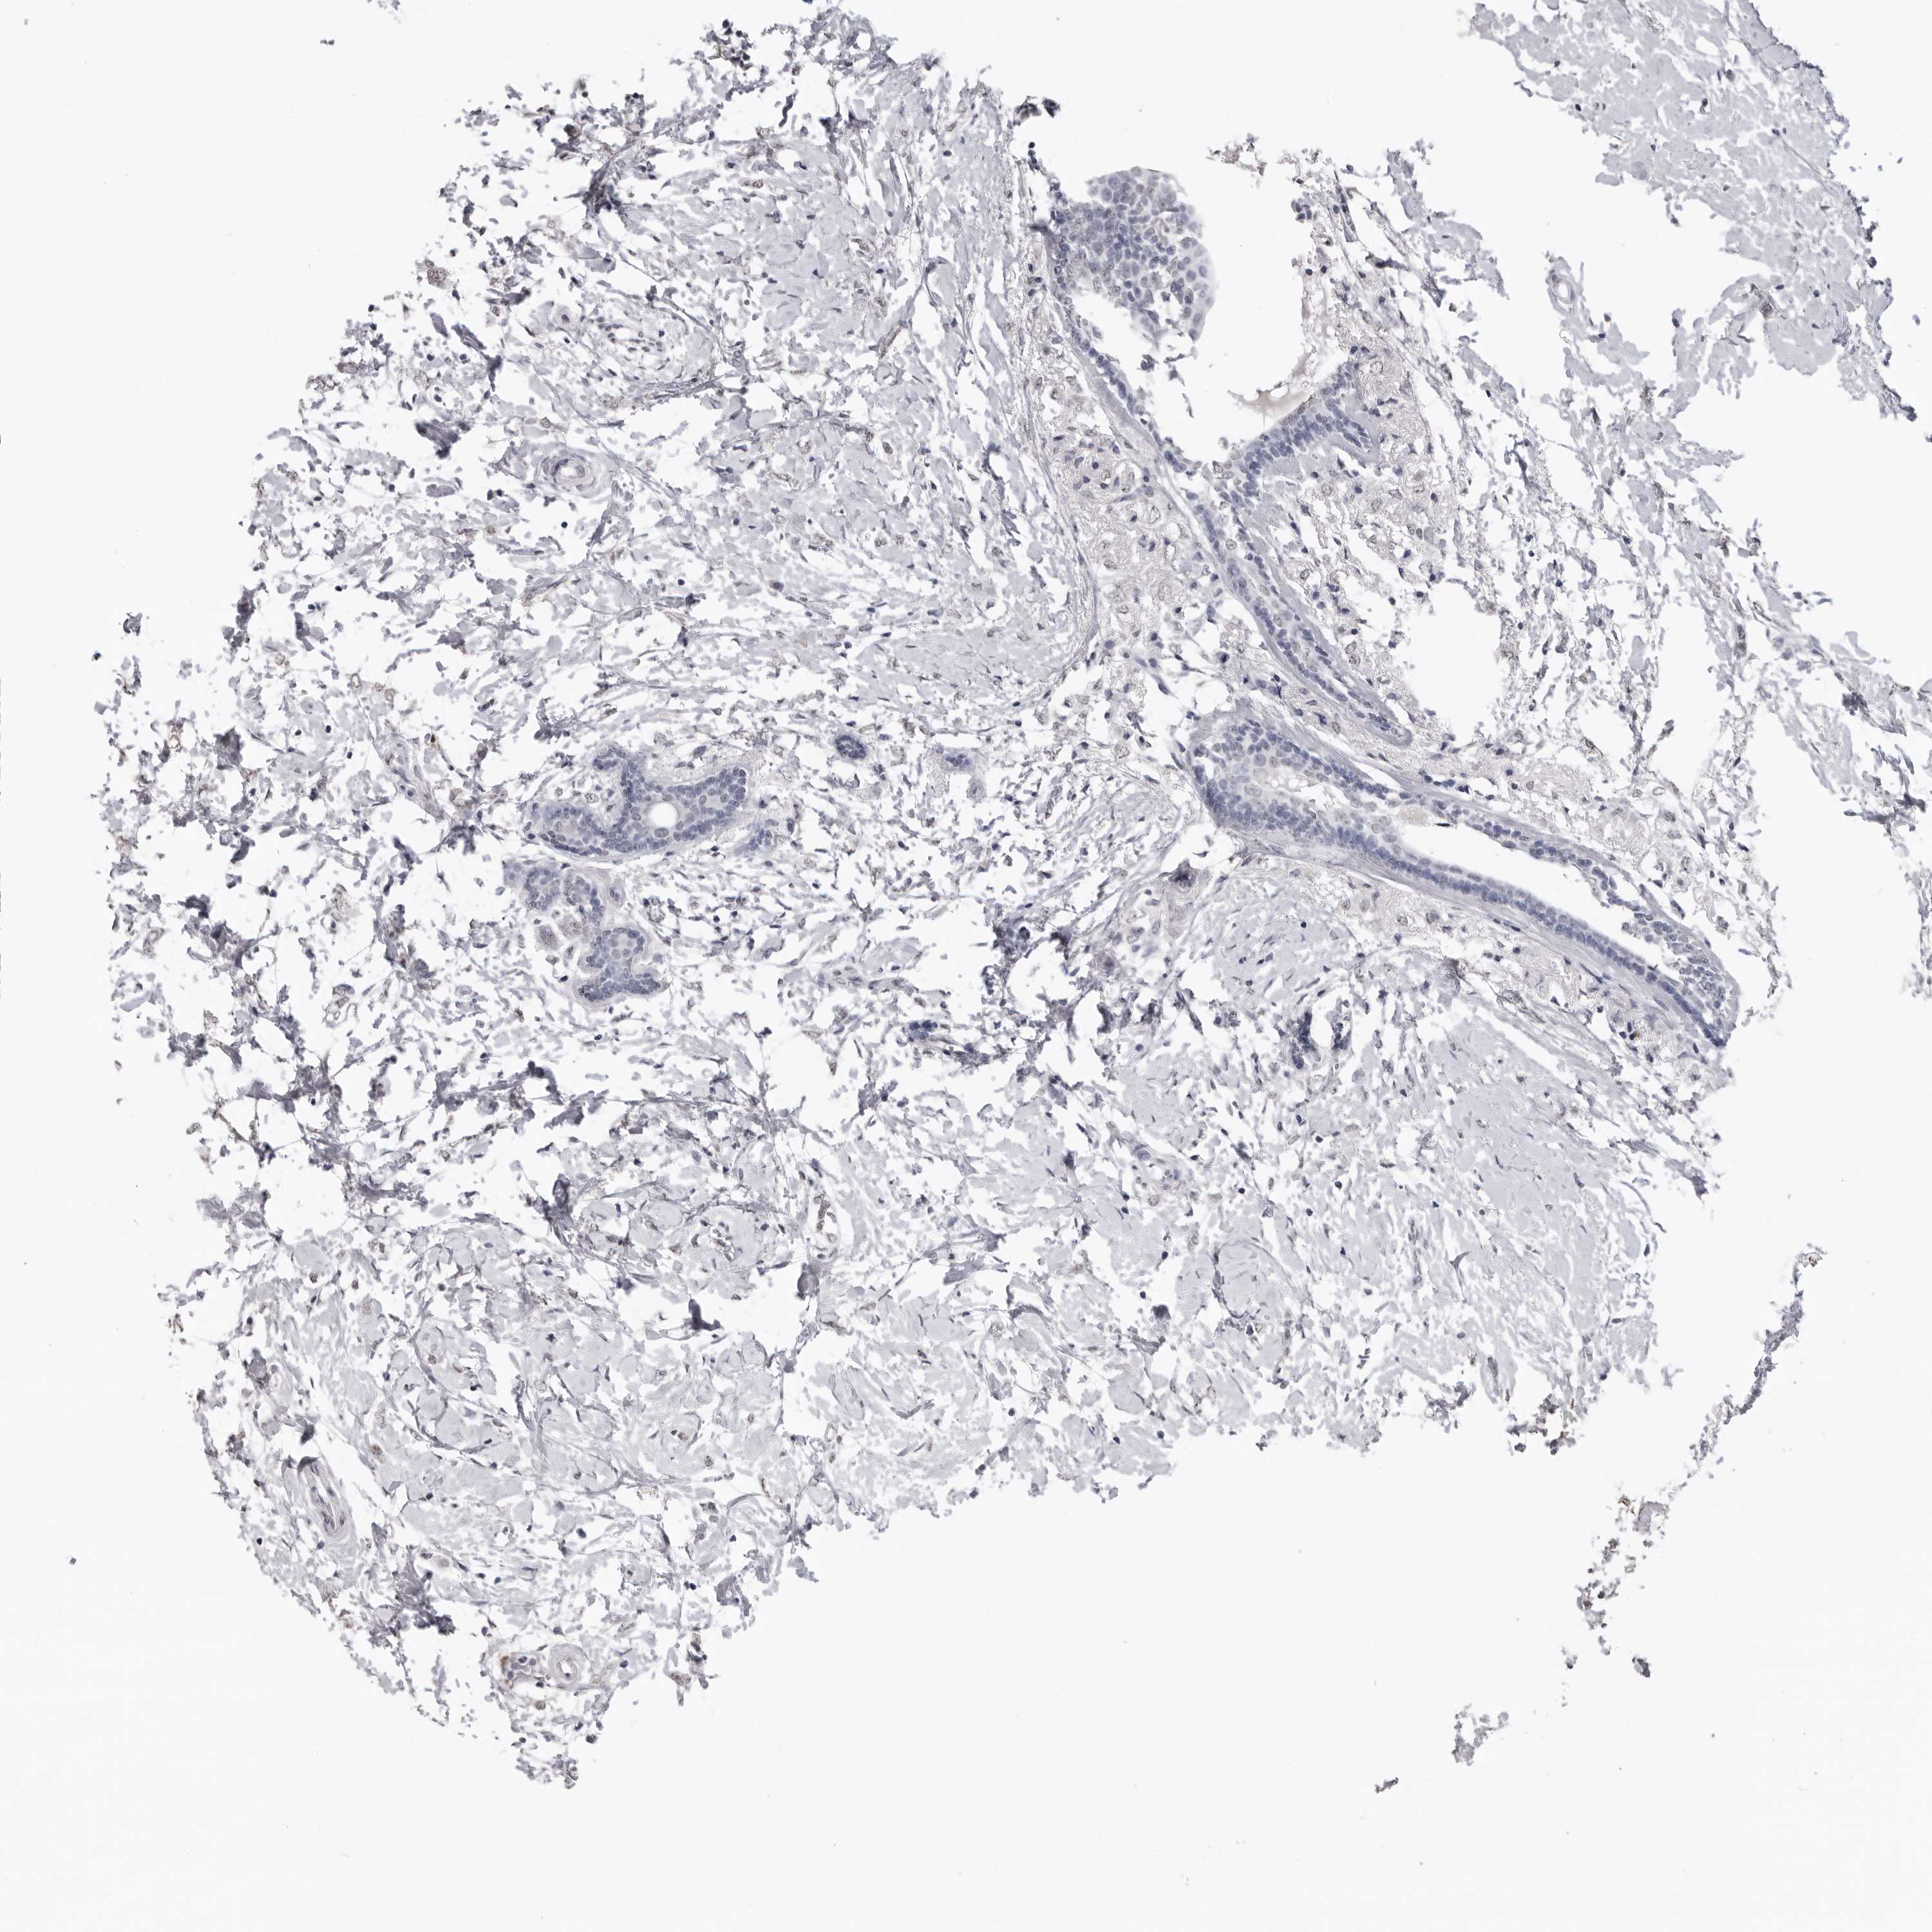

CANCER BREAST CANCER Show tissue menu

BRCA TCGA BRCA VALIDATION PROTEIN EXPRESSION